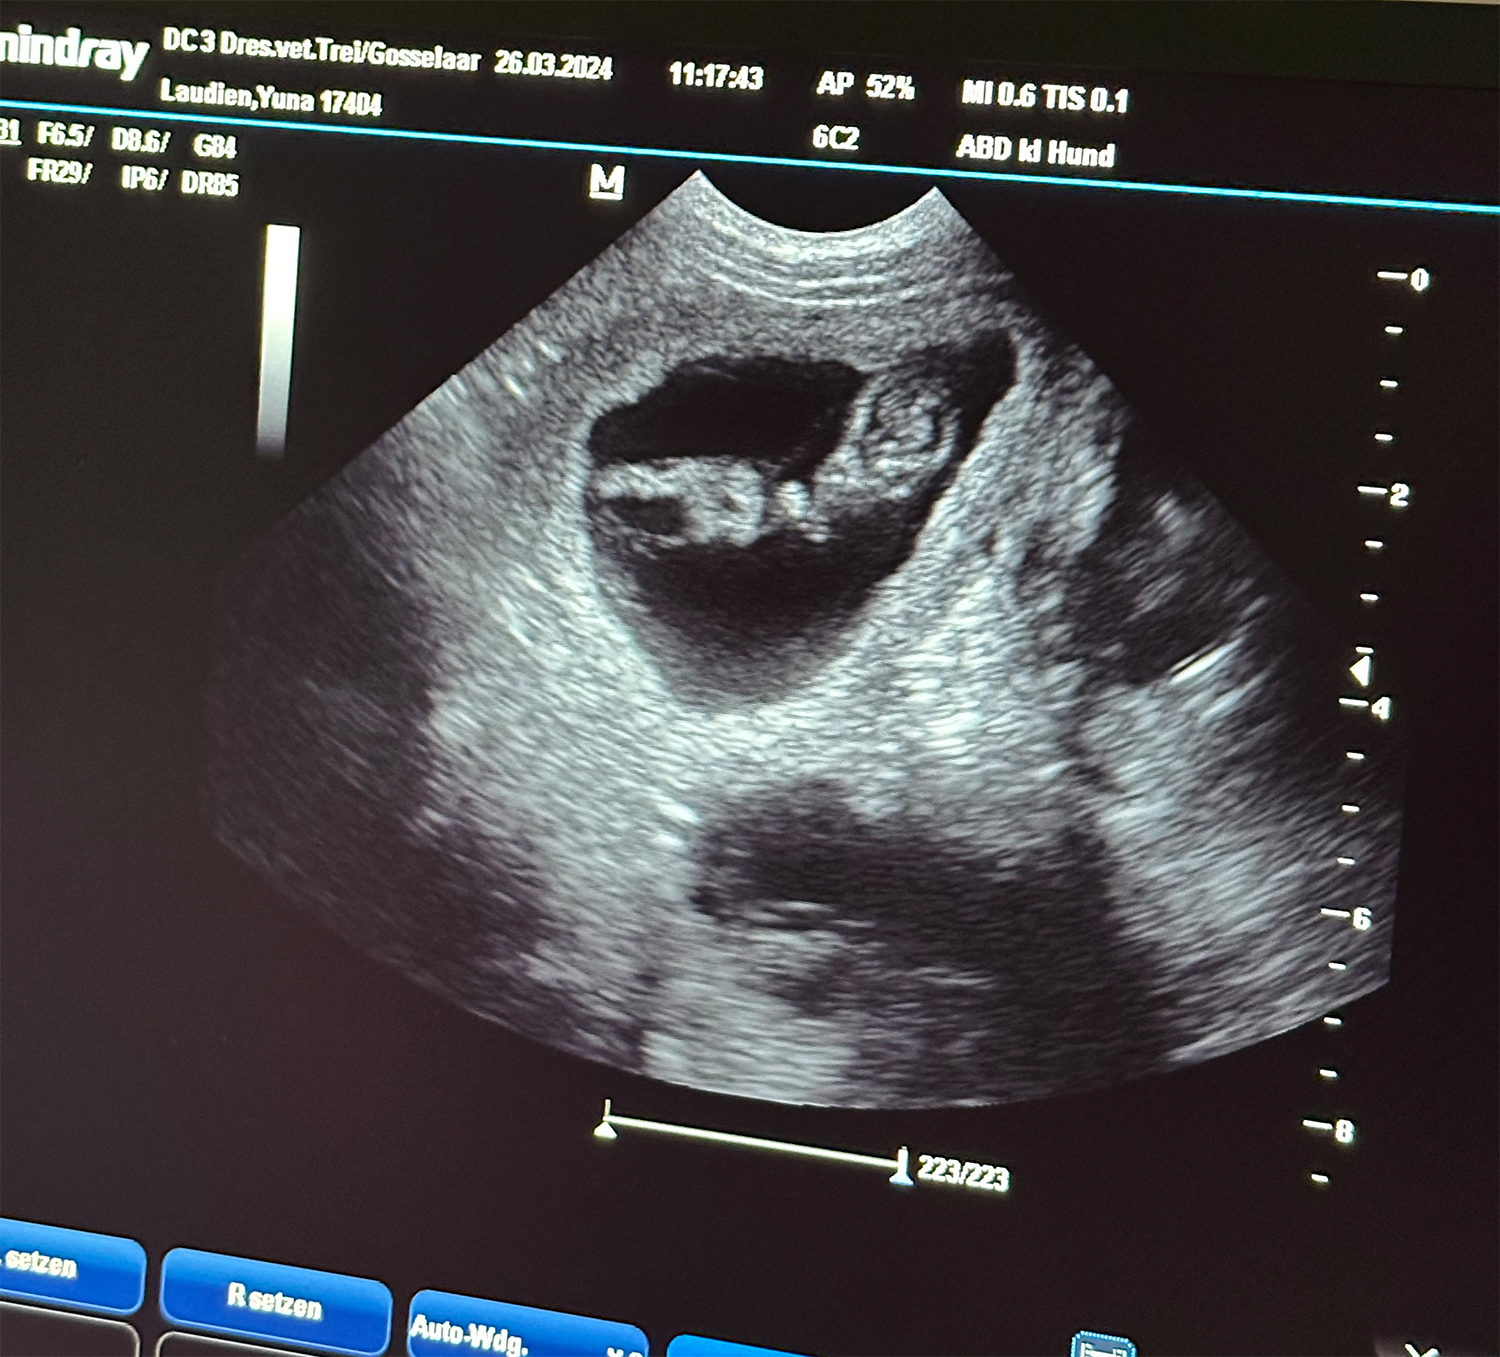

Heute war also der Tag der Tage. Der Tag an dem man Gewissheit bekommt, ob die Hündin aufgenommen hat oder nicht.

Auch wenn in den letzten Tagen einiges für eine Trächtigkeit gesprochen hat, so wollten wir es gerne

von unserer Tierärztin Dr. Insa Gosselaar absegnen lassen.

Beim Ultraschall wurden auf Anhieb einige Fruchtanlagen gesichtet. Die genaue Anzahl wollte ich aber nicht wissen.... ein bisschen Spannung soll uns und den Welpeninteressenten schon noch in den kommenden Wochen erhalten bleiben.  |

Wir freuen uns einfach riesig darüber, dass bald kleine M-Racker den Bagalutenhof besetzen werden.

von unserer Tierärztin Insa Gosselaar absegnen lassen.

Wir freuen uns einfach riesig darüber, dass bald kleine L-Racker den Bagalutenhof besetzen werden.

Bis dato werden wir Yuna fit halten und gut auf unser Essen aufpassen. |